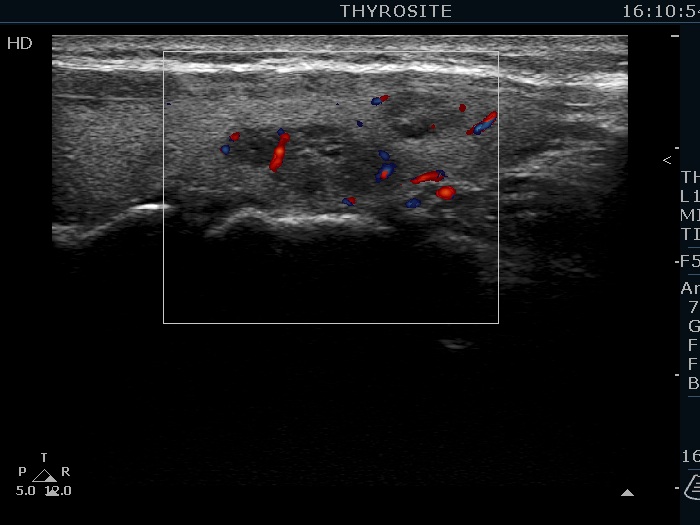

Ultrasonography. The thyroid was echonormal. There were several hypoechoic nodules in the left lobe. The middle one had back wall cystic figures. There were 3 or four discrete, deeply hypoechoic lesions above and lateral to the left lobe in the neck. One of them presented with a hilum-like figure while the others lacked hilum.

The lymph nodes had a non-typical presentation. They lacked a regular hilum.